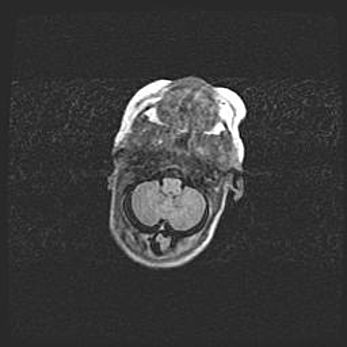

Сообщающаяся гидроцефалия. Кистозная энцефаломаляция головного мозга.

Возраст: 3 месяца 4 дня

Вес: 3100 г

Пол: женский

Окружность головы: 34 см

Срок гестации: 31 неделя

Кистозная энцефаломаляция головного мозга - одна из форм поражения головного мозга в детском возрасте. Характеризуется возникновением множественных и распространённых кист в коре, белом веществе и подкорковых образованиях головного мозга у плодов, новорождённых и детей раннего возраста. Развитие кистозной энцефаломаляции связано с внутриутробной асфиксией и гипотонией, родовой травмой, тромбозом синусов, пороками развития сосудов, инфекциями, сепсисом и другими причинами. Наиболее значимые инфекционные агенты: вирусы простого герпеса, цитомегалии, краснухи, токсоплазмы, энтеробактерии, золотистый стафилококк и другие.